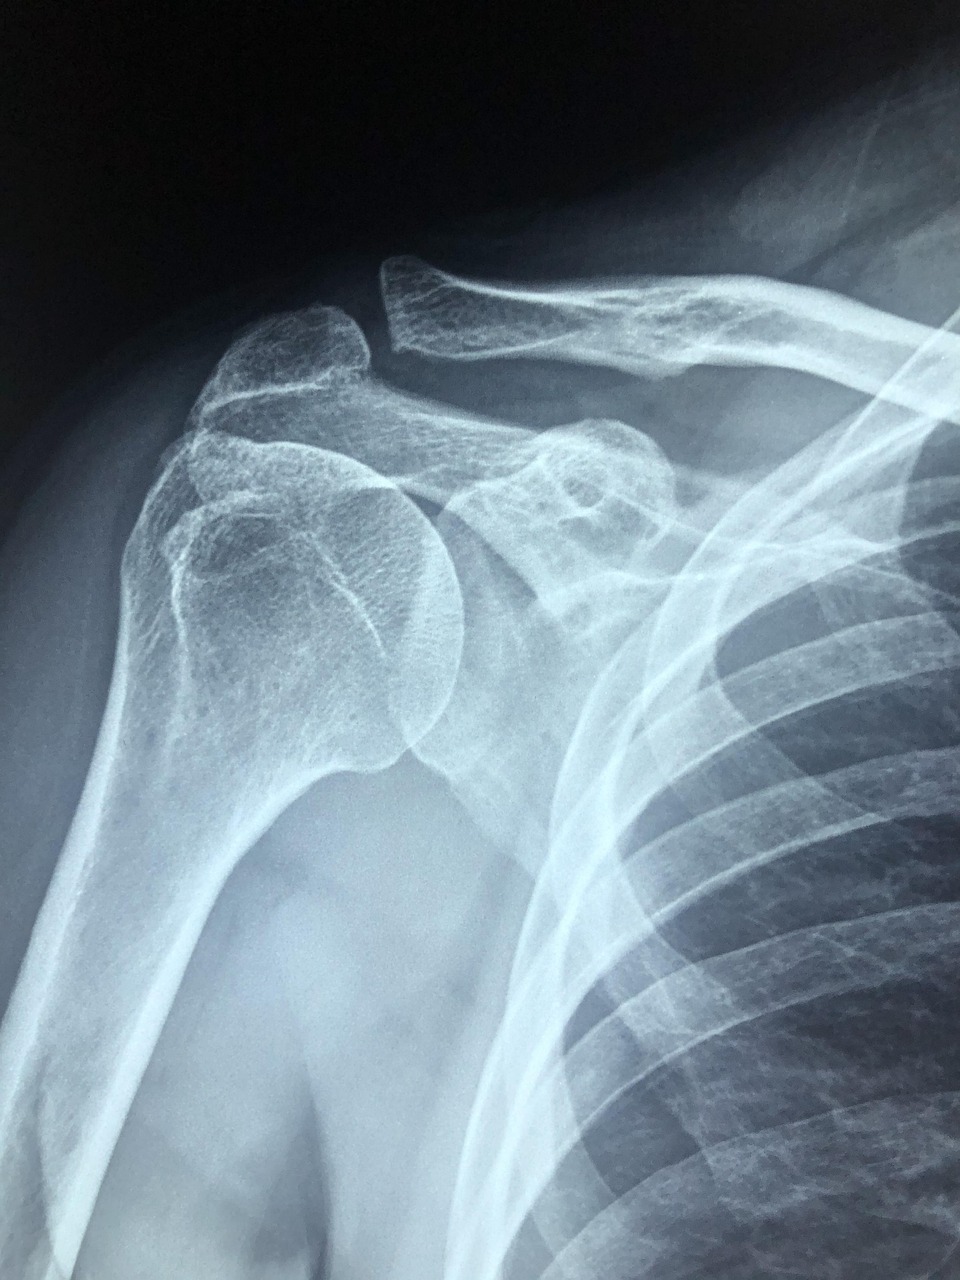

오십견은 50대 이상 중장년층에게 흔하게 나타나는 어깨 질환으로, 점점 팔이 올라가지 않고 통증이 지속되며 일상생활에 큰 불편을 줍니다. 예전에는 오십견 치료법으로 주로 수술이나 장기간의 물리치료가 고려되었지만, 최근에는 비수술적 방법으로도 효과적인 결과를 얻는 경우가 늘고 있습니다. 본 글에서는 2024년 기준으로 가장 효과적인 비수술 치료법들을 자세히 살펴보고, 실제 적용 사례와 주의사항까지 함께 안내드립니다.

2024년 현재 오십견 치료는 단순한 물리치료를 넘어 다양한 비수술 옵션으로 확장되고 있습니다. 대표적으로 많이 사용되는 방법으로는 도수치료, 체외충격파치료(ESWT), 주사치료, 레이저 치료, 재활운동 프로그램, 그리고 최근 인기를 끄는 PRP(자가혈혈소판 주사) 요법 등이 있습니다. 도수치료는 전문 물리치료사가 손으로 관절을 직접 움직이면서 유착을 풀어주는 방법으로, 통증이 적고 회복이 빠르다는 장점이 있습니다. 특히 어깨 관절의 움직임을 제한하는 유착성 관절낭염의 경우, 도수치료를 통해 유착을 점진적으로 해소할 수 있어 수술 없이도 큰 효과를 볼 수 있습니다. 체외충격파치료(ESWT)는 통증 부위에 고에너지 음파를 전달해 염증을 줄이고 혈류를 촉진하는 방식입니다. 오십견으로 인한 어깨 주변 석회화나 염증성 변화에 효과적이며, 1~2주 간격으로 3~5회 정도 진행하면 통증 완화와 함께 움직임 개선이 가능합니다. 또한 스테로이드 주사나 점액낭 주사 등 다양한 약물치료도 병행될 수 있습니다. 이러한 주사요법은 염증이 심하거나 통증이 일상생활을 방해하는 경우에 단기적으로 큰 효과를 보이며, 특히 다른 치료와 병행하면 시너지 효과가 있습니다. 최근에는 PRP 요법이 주목받고 있습니다. 자가혈을 뽑아 혈소판 농축액을 추출한 후 손상된 조직에 주사하여 회복을 유도하는 방식으로, 부작용이 적고 자연적인 재생을 유도하기 때문에 장기적인 효과를 기대할 수 있습니다. 이는 스포츠 손상 치료에도 널리 사용되는 방식으로, 오십견에서도 점점 활용도가 증가하고 있습니다. 그 외에도 한방치료(침술, 뜸치료), 통증 유발점 주사치료(TPI), 정밀 초음파 유도하 도수치료 등의 융합요법도 환자의 상태에 따라 병행되며, 최근 병원에서는 이들 치료를 통합적으로 운영하는 프로그램이 많아지고 있습니다.